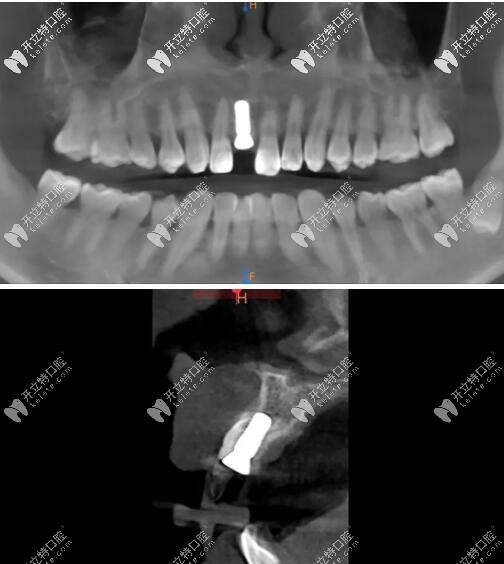

影像學檢查

門牙磕斷傷及牙根影像學檢查

被磕的牙冠根向折裂,直達骨下;

牙根骨量充足;

牙長軸和牙槽骨的方向基本一致。

術(shù)后CBCT顯示植入正確的三維位置,種植體唇側(cè)骨量充足;

瑞士iti鈦親水BL 4.1mm*10mm種植體